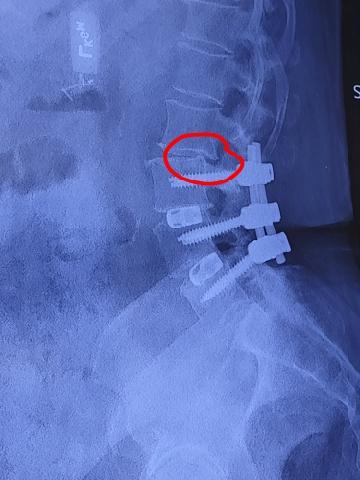

I had back surgery on April 24, 2024 for spinal stenosis and degenerative disc disease. My doctor placed two rods and six pins in my back. A year later, he recommended another surgery to extend the hardware from L3 to the pelvic bone—longer rods and four more pins. After I explained everything to my friend Kevin, he encouraged me to start taking BoneX. Six months later, my follow-up showed new bone growth, and I no longer needed the extension surgery. Instead, my doctor removed the rods and pins that were there—and even let me keep them to show my family and friends!